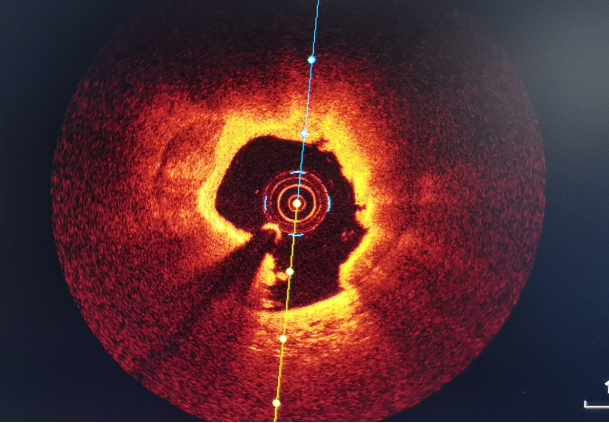

术中影像

消蚀前:管腔面积<1.5mm²,钙化。

支架后:管腔面积>6mm²,支架贴壁良好。

激光消蚀后前降支病变处最大管腔>6mm²,未见血栓及夹层,支架植入后复查CTO支架贴壁良好,扩张充分,未见血肿及夹层,手术效果良好。